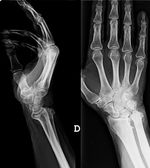

A la imatge de radiologia convencional en projeccions anteroposterior, i perfil de mà i canell objectivem una artropatia degenerativa evolucionada amb marcada desestructuració articular radiocubital distal, amb allargament i elevació del cúbit respecte al radi (cubit plus), i desviació dorsal del cap cubital (fig. 2), probablement a causa d'una seqüela d'una fractura ràdio distal antiga, no referenciada pel pacient, amb escurçament del radi i subluxació del cap cubital.